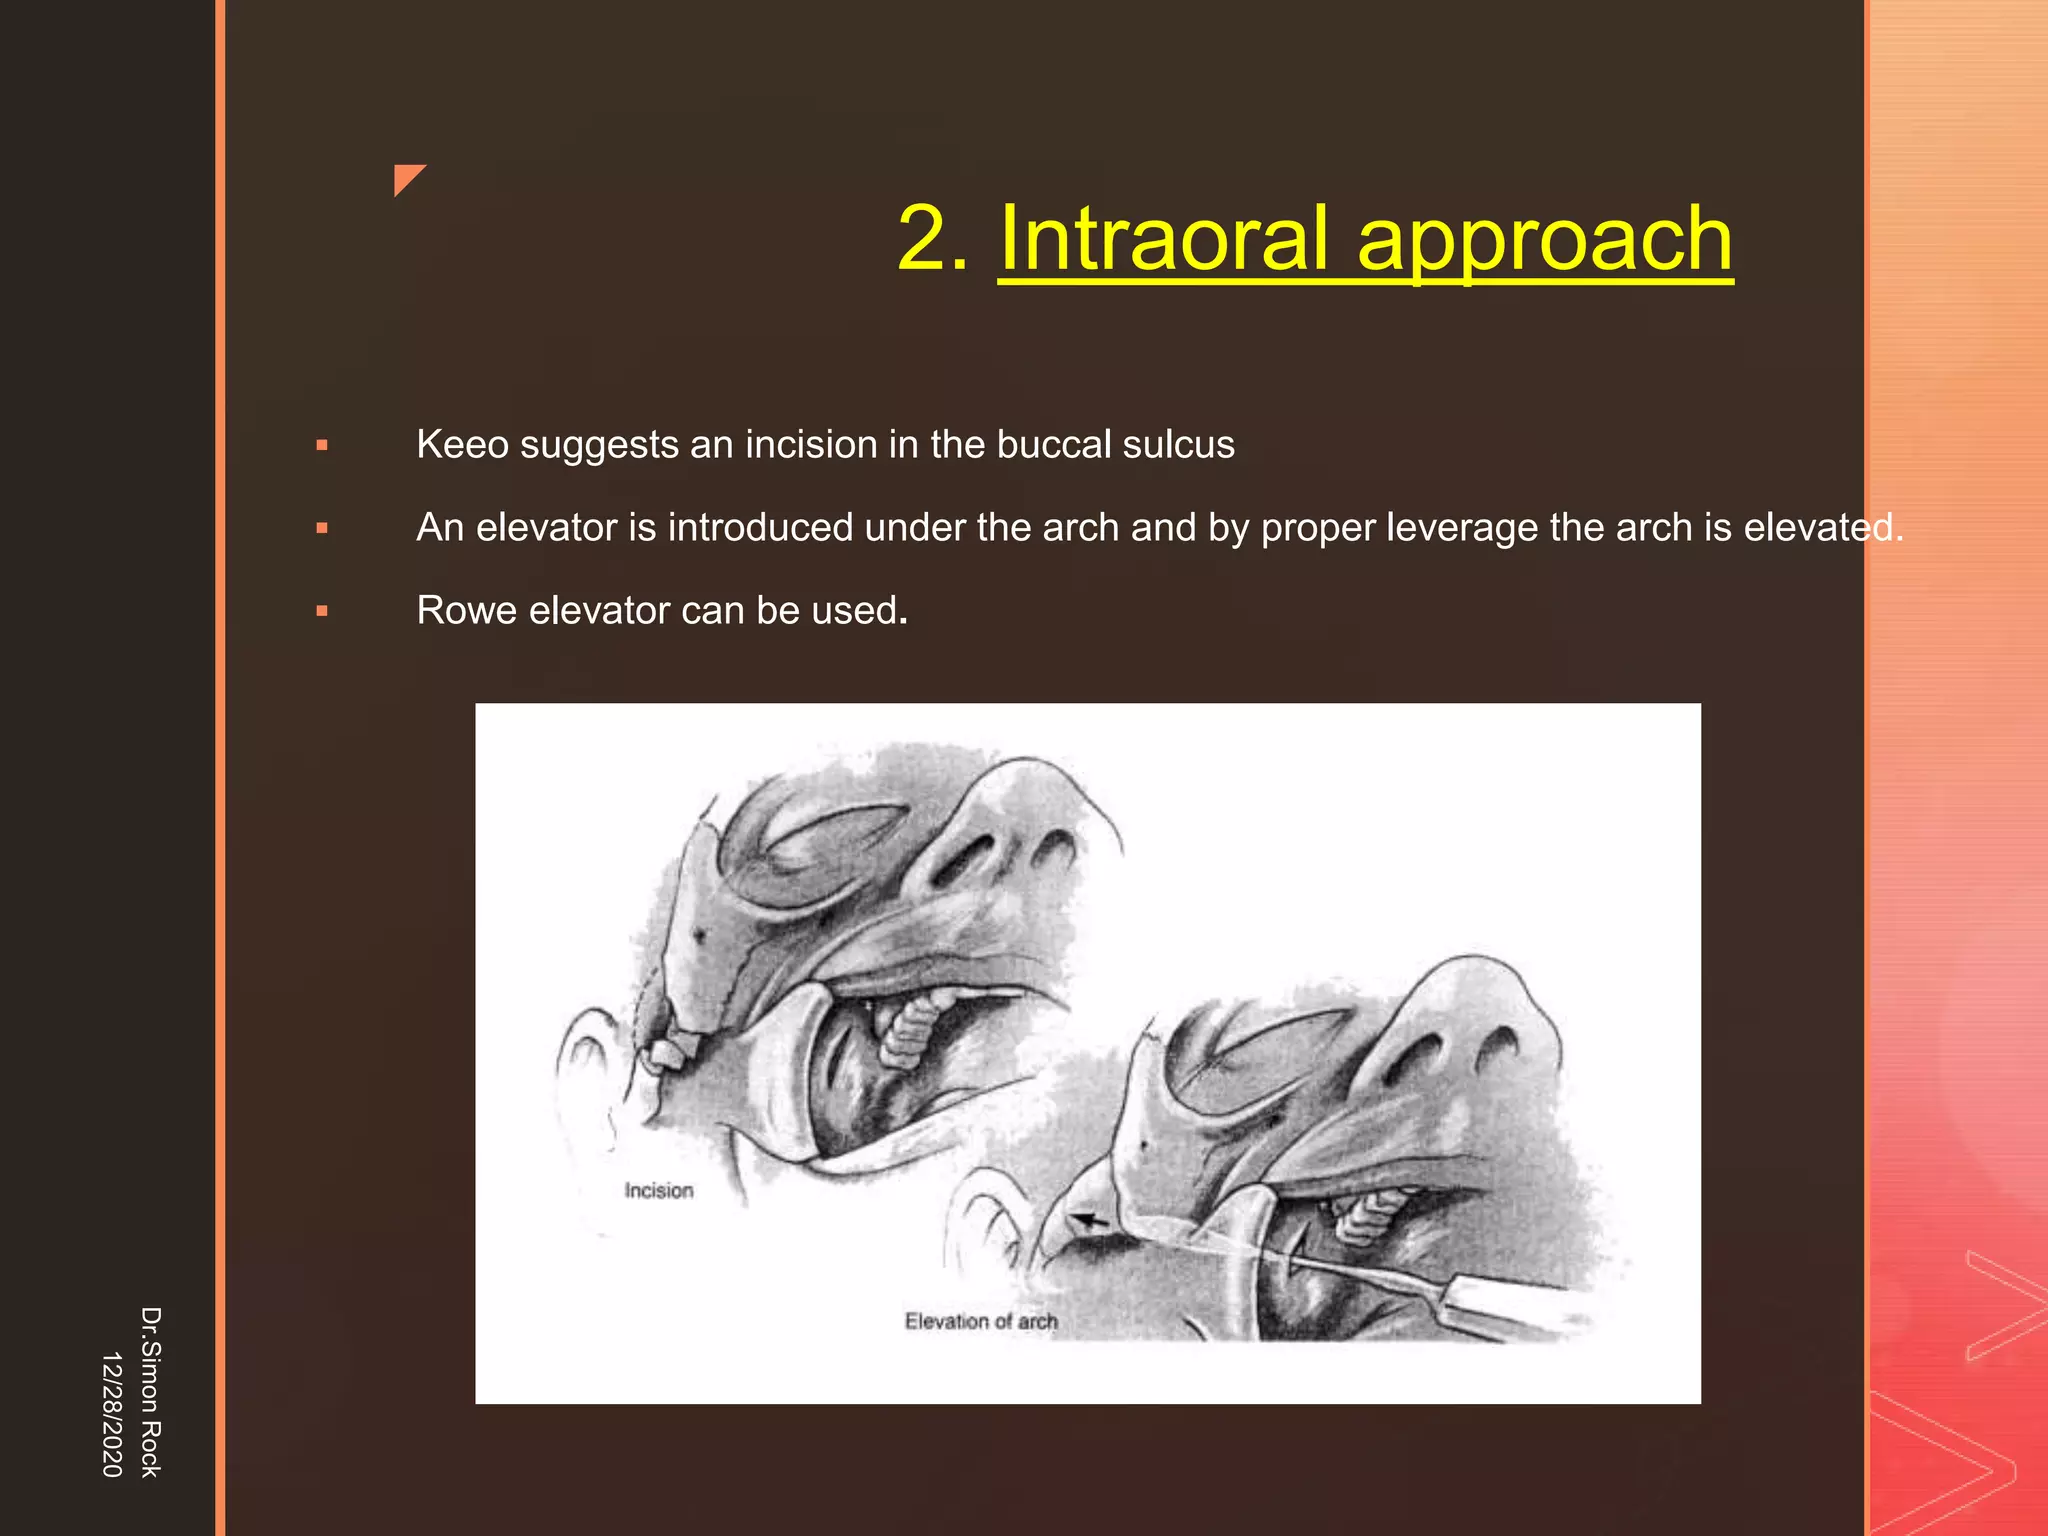

This document discusses the anatomy and fractures of the zygomatic bone. It notes that the zygoma forms the cheekbone and articulates with several other facial bones. Zygomatic fractures most commonly occur in the arch or body due to blunt trauma. Diagnosis involves checking for diplopia, ecchymosis, and other signs of orbital or facial bone involvement. Treatment may involve closed or open reduction based on the severity of displacement. Closed reduction techniques try to elevate the bone back into position without surgery, while open reduction requires surgical exposure and fixation of the fracture site.